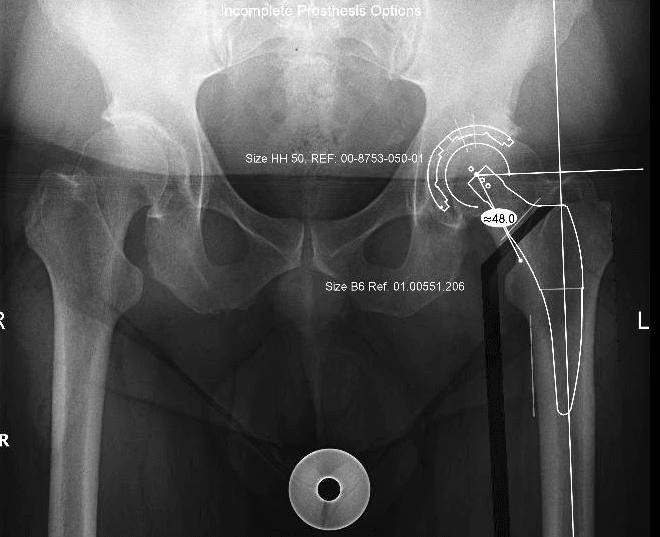

L’intervento di artroprotesi d’anca prevede la sostituzione dell’articolazione dell’anca mediante l’impianto di componenti protesiche in leghe metalliche, come il titanio, accoppiati a materiali plastici (polietilene di ultima generazione) e/o ceramiche. Questo processo include la sostituzione del femore prossimale (testa e collo) e il rivestimento della cavità acetabolare del bacino. L’obiettivo principale di questa procedura è ripristinare un’articolazione stabile e funzionale, migliorando significativamente la capacità di movimento del paziente, alleviando il dolore e migliorando la qualità della vita.

Esistono diverse vie d’accesso chirurgiche per l’artroplastica d’anca; quelle preferite nel nostro centro, a seconda delle caratteristiche del paziente, sono la via postero-laterale e la via anteriore. Ognuna di queste vie ha caratteristiche e vantaggi specifici, e la scelta è sempre basata sulle esigenze individuali del paziente.